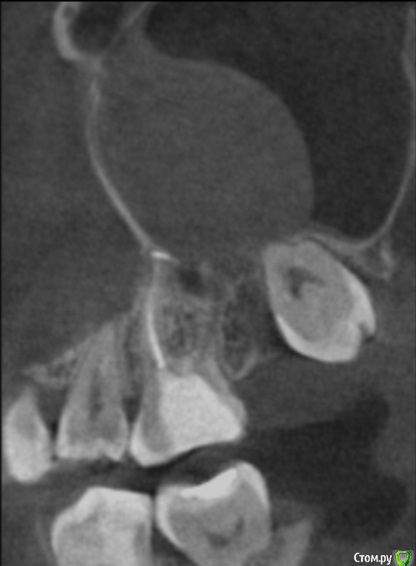

Снимок спустя 1,5 месяца после цистогайморотомии.

post-50922-0-04327700-1517780426_thumb.jpg

В связи с чем я начала перелечивать каналы 26 зуба у нового стоматолога. Врач предупредила, что лечение таких зубов с хр.периодонтитом долгое, и окончательная пломбировка к/к будет произведена только тогда, когда зуб перестанет болеть на лечебной пасте.